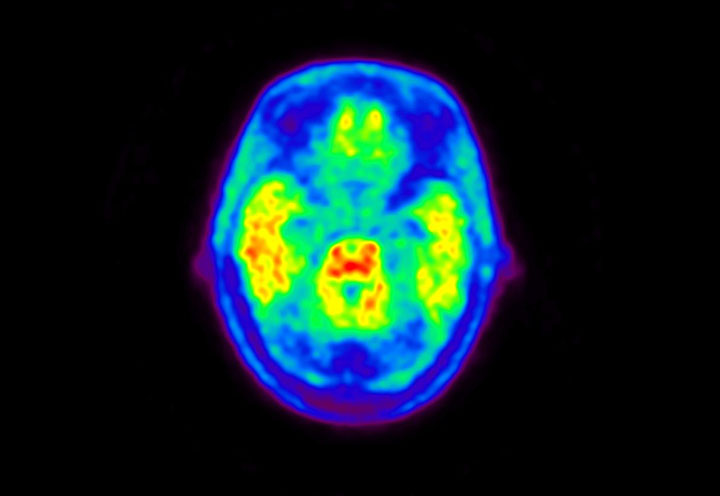

Head / Case5 : Amyloid

Courtesy : Kindai University Hospital

- Imaging protocol

- Injected dose: 4.27 MBq/kg, 18F-Flutemetamol

- Uptake time: 99 minutes

- Scan time: 20 minutes